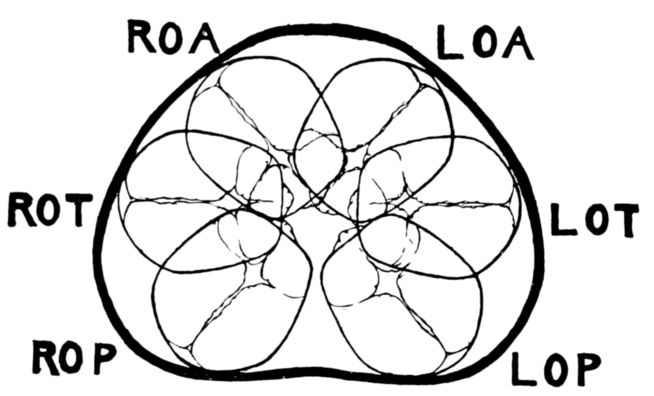

| 54. | Diagram of six positions in a vertex presentation | 222 |

| 55. | Diagram of six positions in a face presentation | 223 |

| 56. | Diagram of six positions in a breech presentation | 223 |